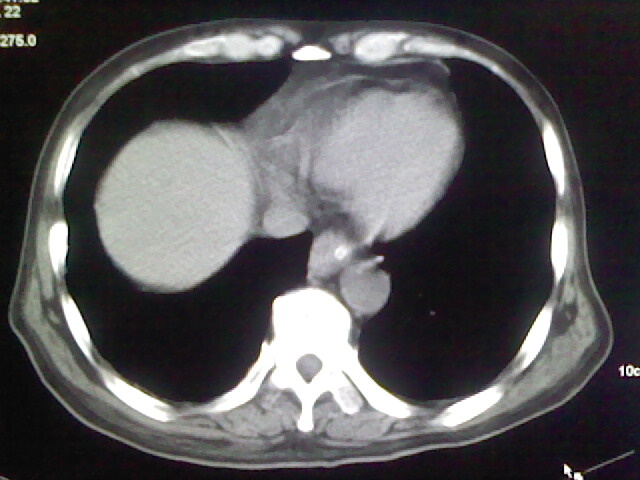

男,70岁,脑出血,长期卧床,左侧背部可触及肿块

肺部感染,背部筋膜增厚,考虑坠积性水肿或炎症

右侧肺部见片状密度增高影,边缘模糊。考虑炎症。另食管壁增厚。